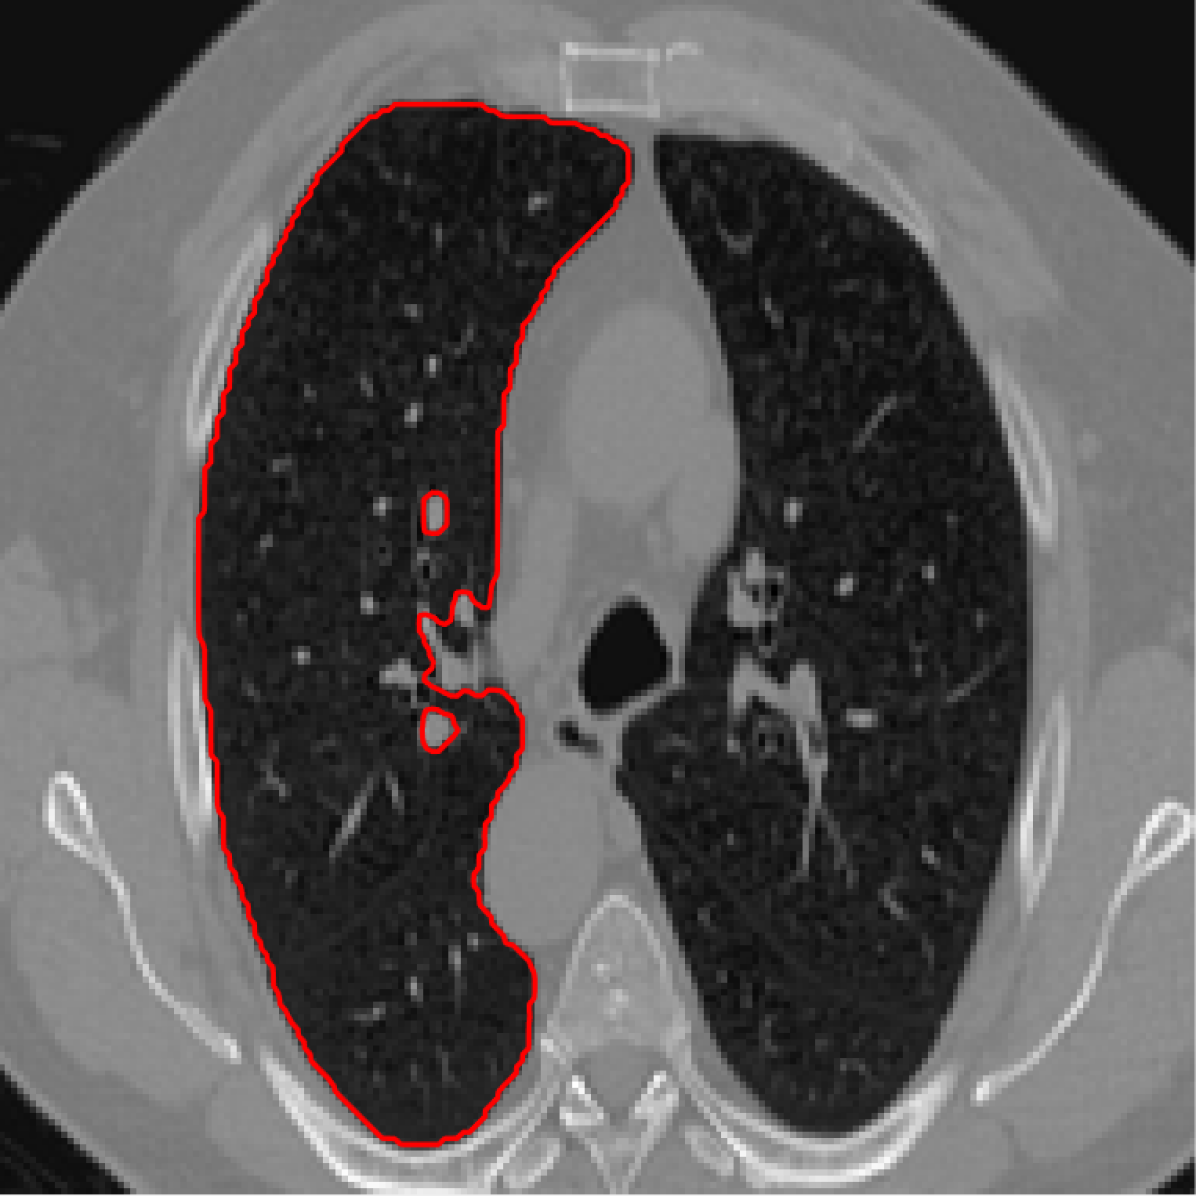

Figure 3: A sample result on the Lung data. We display the input image with the user input \mathcal{M}, the ground truth (GT) and results from the four methods. Moreover, we show comparisons with the model (4) solved in a variational framework with both Total Variation (TV) and Euler Elastica as explicit regularisation, as well as a comparison with the model solved in a Deep Image Prior framework.

In Figures 3 and 4 we show two select images from the test set for the Lung images to qualitatively show some results. To begin, we show some results of the model (1) solved with a Total Variation (TV) [21] regulariser, and with a Euler Elastica [22] regulariser. In addition, we show a result with the model (1) in a typical Deep Image Prior framework (i.e. training a network specifically for that image without the explicit regularisation in the loss function, employing early stopping). We see that the result from M4 is an improvement over the TV and Elastica models, whereas results from the DIP example is comparable. However, the DIP example requires a new network trained specifically for the new image, whereas our result is acquired after training. In addition to the explicit regularisation comparison, we also display the results from the four methods (all of which are trained previously on 222 images and used for prediction). Moreover some quantitative results are shown in table 1, which shows the mean DICE score and standard deviation on the 16 images in the test set.